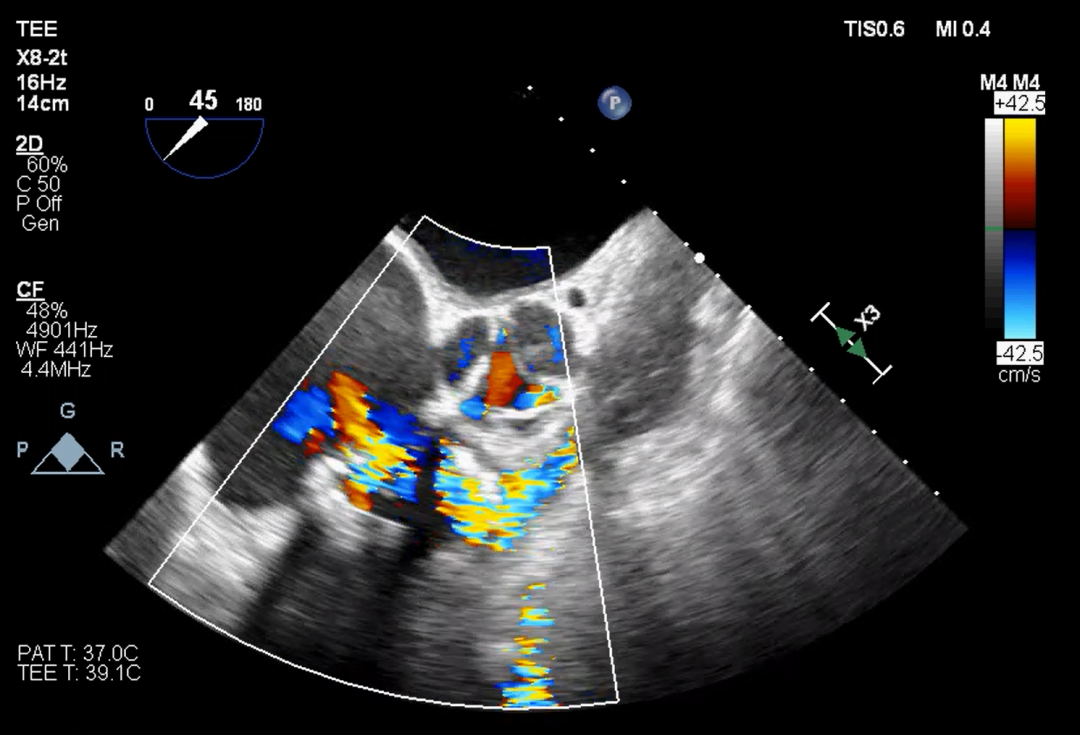

超声提示

本例患者15年前因三尖瓣增厚伴重度反流,接受31#三尖瓣生物瓣置换。该类型的外科生物瓣在影像下透视性差,术中难以清晰捕捉其形态和位置。同时,其右心室狭小,留给介入瓣操作的空间有限,使得本次手术难度升级。宁波市第一医院心外科励峰主任团队凭借丰富的瓣膜外科手术经验,成功经右房途径TTViV植入一枚29#的J-Valve瓣膜。J-Valve经心尖介入瓣膜系统,在治疗生物瓣衰败的改为患者中行瓣中瓣植入术可以取得良好的临床效果。其独特的定位件设计,能够准确牢固地锚定在原生物瓣的瓣脚上,降低瓣膜移位的发生率。术后,患者三尖瓣跨瓣压差、反流及右房压均明显改善,即刻获益。